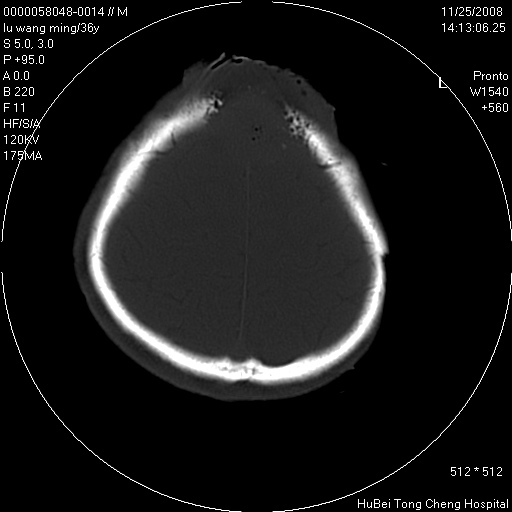

患者 男,36岁。头部烧伤36年伴溃烂,经久不愈。患者几个月大时,倒入火炉不幸烧伤头部,后长期溃烂,经久不愈。

临床诊断:1)头皮烧伤并感染。2)颅骨病损?

颅脑ct轴位平扫(层厚、层距均匀10mm),图像如下:

以骨质破坏为为,边缘呈虫噬样改变,多砂粒样钙钙化或死骨,伴软组织及硬膜外积脓,考虑为结核感染可能性大,建议细菌培养。

额顶局部骨质破坏缺损

骨质破坏,边缘呈虫噬样改变,结合患者明确烧伤史,经久不愈,考虑软组织化脓性感染,颅骨损害伴硬膜下积脓。